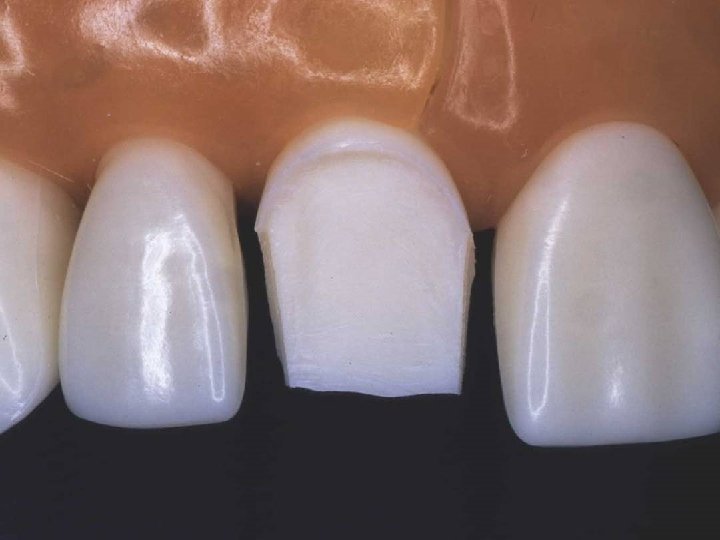

Gingival facial reduction

Initial proximal reduction

Lingual axial reduction